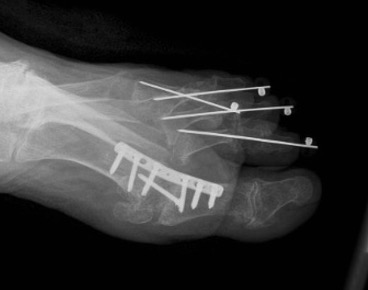

Operative Options

Synovectomy / Weil's osteotomy / Fowler's procedure (excision arthroplasty)

- Weil osteotomy in 72 RA feet

- 88% good or excellent results

- recurrent / persistent subluxation in 14%

Horita et al Foot Ankle Int 2018

- 16 resection arthroplasty v 18 Weil osteotomy in RA

- resection: outcome score 84, recurrence 3 feet

- osteotomy: outcome score 90, recurrence 1 foot

Fowler's Procedure - metatarsal head excision

Dorsal transverse skin excision just proximal to toe webs

- can be performed via transverse plantar ellipse

- with severe dislocation may be easier to approach through plantar aspect

Extensor tenotomy

Cascading excision of II - V metatarsal heads

- dorsal distal to plantar proximal

- contoured on plantar surface to give rounded surface